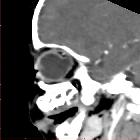

In posterior ocular coloboma, on CT or MRI, the affected globe is usually small with a focal posterior defect in the globe with vitreous herniation . A retrobulbar fluid-density cyst may be present .